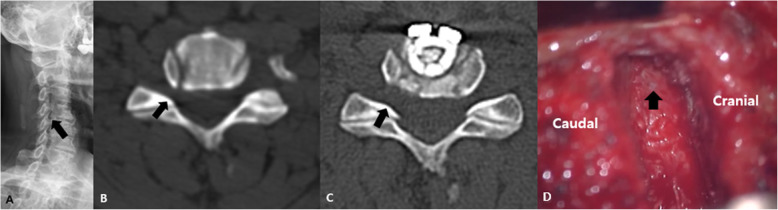

Fig. 2.

A: Cervical spine oblique radiographs at C4–5 (black arrow). B: Cervical spine CT (axial view) shows right foraminal stenosis (black arrow). C: ACDF with UPR was performed, and the right foramen was widened on post-operative CT (black arrow). D: The nerve root was decompressed by completely removing the uncinate process (black arrow)

Between January 2011 and December 2015, 578 patients who underwent ACDF for cervical spondylotic disease at our institution were collected. Among them, we excluded 473 patients whose follow-up period was less than 2 years or the surgery level was two levels or more. In this retrospective study, 105 consecutive patients with single-level cervical spondylotic disease who underwent primary ACDF with a cage-and-plate construct between January 2011 and December 2015 at the author’s institution were included (Fig. 1). This study was approved by the Institutional Review Board of our hospital. The uncinate process was randomly removed totally according to the technical preference of the single surgeon (Fig. 2). Thus, we defined ACDF with UPR as complete unilateral or bilateral removal of the uncinate process, while ACDF without UPR was defined as the conventional removal of only the anterior and posterior parts of the uncinate process or no removal of the uncinate process. This was confirmed with postoperative computed tomography scans. The patients were divided into two groups: 37 patients underwent ACDF with complete UPR and 68 patients were treated with ACDF without UPR. For statistically matched pairs analysis, ACDF with UPR group (24 patients) and ACDF without UPR (24 patients) were compared. The inclusion criteria included the following: 1) patients with symptoms of degenerative cervical disease; 2) patients who received primary ACDF with UPR at only one level; and 3) a follow-up period greater than 24 months. The exclusion criteria were as follows: 1) patients who had previous cervical spine surgery due to ossification of posterior longitudinal ligaments, fractures, tumors, etc.; 2) patients who underwent ACDF for more than two levels; and 3) a follow-up period less than 24 months.